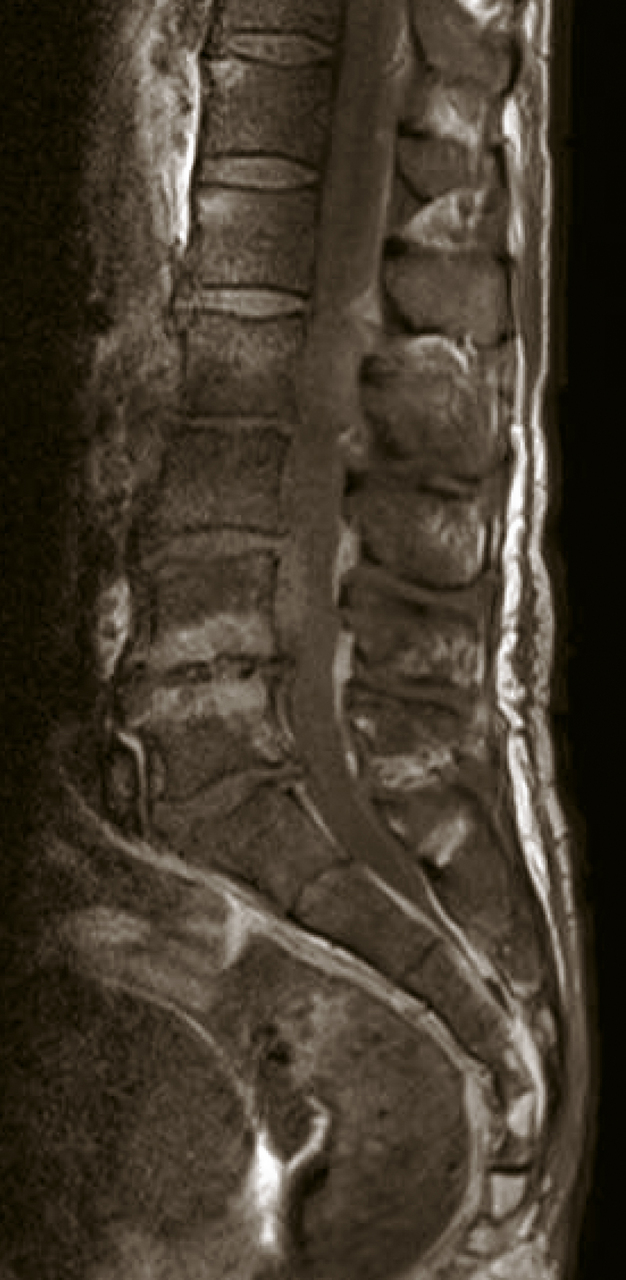

Homme de 50 ans souffrant de lombalgies et de fièvre. Quel est votre diagnostic ? Lombodiscarthrose Arthrose pseudo-pottique Hyperostose vertébrale engainante Spondylodiscite Spondyloarthrite OK Valider mes réponses